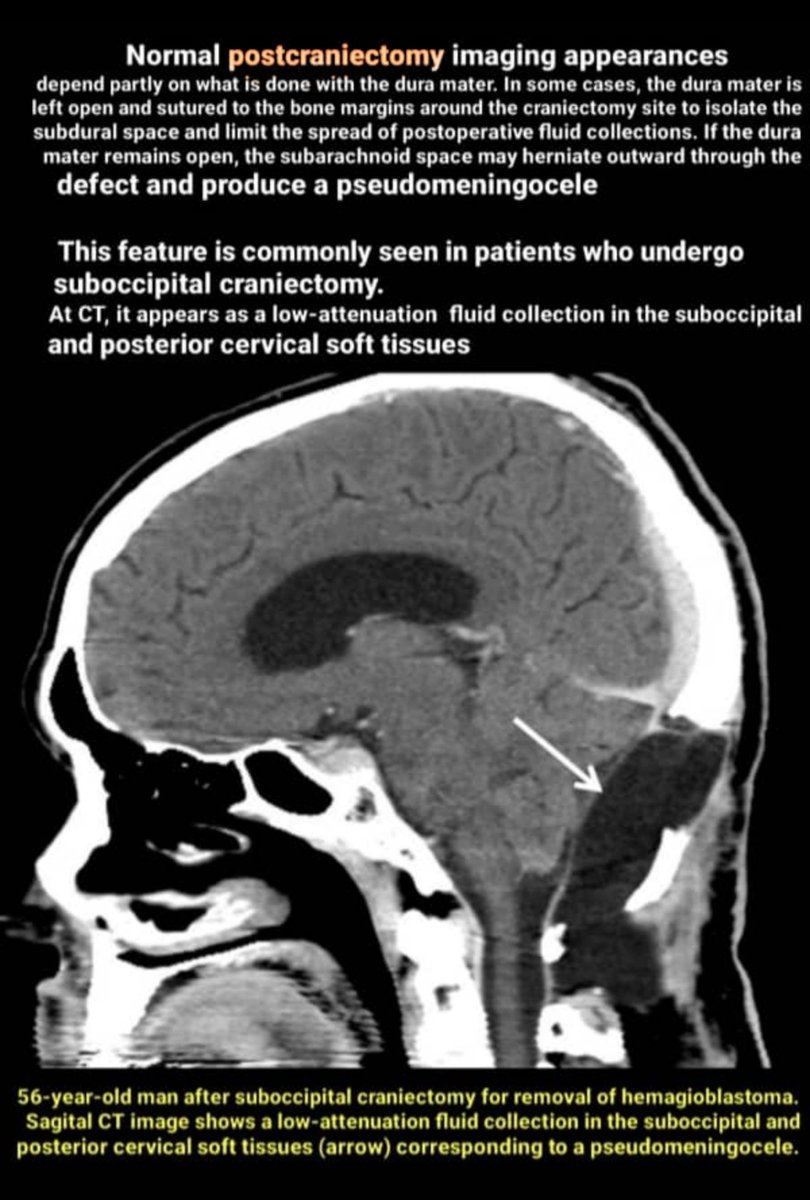

It's important to be familiar with normal post-op imaging findings following cranial surgeries with different surgical techniques such as :

burr holes, craniotomy, craniectomy,and cranioplasty.

I show you different normal post-op images in a row as remarks. I hope you like itπŸ‘

Craniectomy is the removal of a portion of the skull without subsequent replacement of the bone. It may be performed to remove an infected bone flap from previous craniotomy or a tumor that has infiltrated the calvaria. It may perform as part of a suboccipital approach